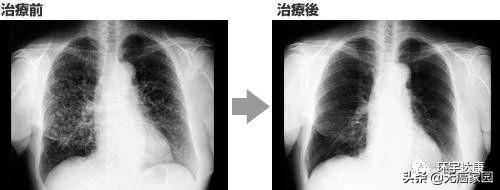

晚期肺癌,NK细胞治疗联合化疗肿瘤消失

56岁,男性患者被确诊为广泛期小细胞肺癌,就像上个案例中的一样,小细胞肺癌,特别是广泛期的治疗方案非常有限,也最多只能进行6个疗程的化疗,之后的治疗可能就不再那么有效!

于是,医生制定了详细的治疗方案,进行4个疗程化疗和4次高度活化NK细胞回输后,第一次进行治疗后的CT复查,结果显示,肿瘤缩小到了原来的1/8。

主治医生预言:下次复查时,肿瘤会消失。果不其然,3个月后的CT检查显示肿瘤消失了!

之后,每月一次进行NK细胞回输,用于维持病情稳定,共进行了三次回输,然后就停止了所有的治疗。

每隔三个月进行一次复查随访,每次CT检查显示并无异常,距发病第六年的CT复查中,仍旧没有发现任何异常及复发的迹象。医生说:“这简直就是奇迹!甚至可以宣布癌症已经根治,之后无须进行复查随访。”